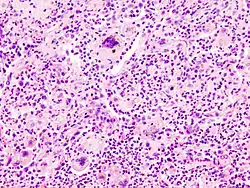

- Maligne - Infiltrativ-invasiv wachsend, rasch wachsend -> Nekrosen, unreife, atypische Zellen, Metastasen.

Kriterien der Malignität

- Makroskopisch: Infiltrierend/diffus wachsend

- Histologisch: Nekrosen, Kapillarisierung (Neoangiogenese), Aufhebung der normalen Histologie.

- Zytologisch: Polymorphie, basophiles Cytoplasma, erhöhte Kern/Plasmarelation

- Nukleär: Polymorphie, Polychromasie, Hyperchromasie, Aneuploidie, (vergrößerte) Nukleolen, vermehrt Mitosen, atypische Mitosen, erhöhter Proliferationsindex (Ki-67 = MIB-1).